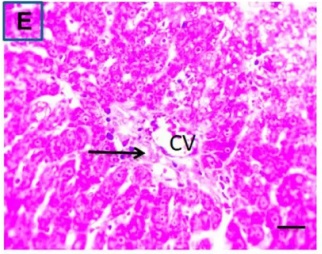

Put the liver tissue section under a microscope, and you can see that cisplatin can cause liver congestion (the blood that should return to the heart is blocked and stagnates in the hepatic veins), cell degeneration (vacuoles appear, which is the earliest change in cellular injury), apoptosis and necrosis, but these conditions can also be alleviated by using Ganoderma lucidum.

Figure 2 Effects of cisplatin and Ganoderma lucidum on hepatocytes